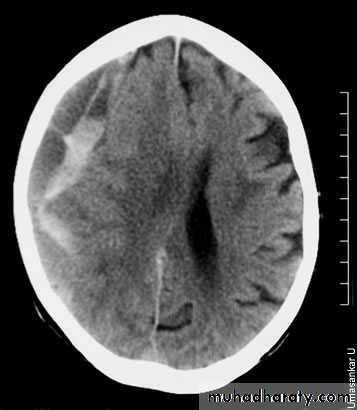

There is an acute on chronic right subdural collection with a depth of at least 2.5 cm. There is associated oedema of the right cerebral hemisphere with an approximately 1 cm midline shift to the left. This is an acute on chronic subdural haemorrhage. Patients with a subdural haematoma do not always have a history of falls.

There is evidence of widening of the cortical sulci, subarachnoid spaces, and ventricular cistern denoting involutional brain changes. The occipital horn of the left lateral ventricle is noticeably dilated and associated with a large cerebral spinal fluid space, replacing brain tissue of the left occipital lobe. This may denote a sequel of a previous large infarction. There is cerebral atrophy. Cerebral atrophy is more common in patients with dementia, but it is not sensitive or specific enough to be used as a diagnostic marker for dementia. CT scans are used to exclude structural and potentially treatable causes of dementia, such as brain tumours and normal pressure hydrocephalus.